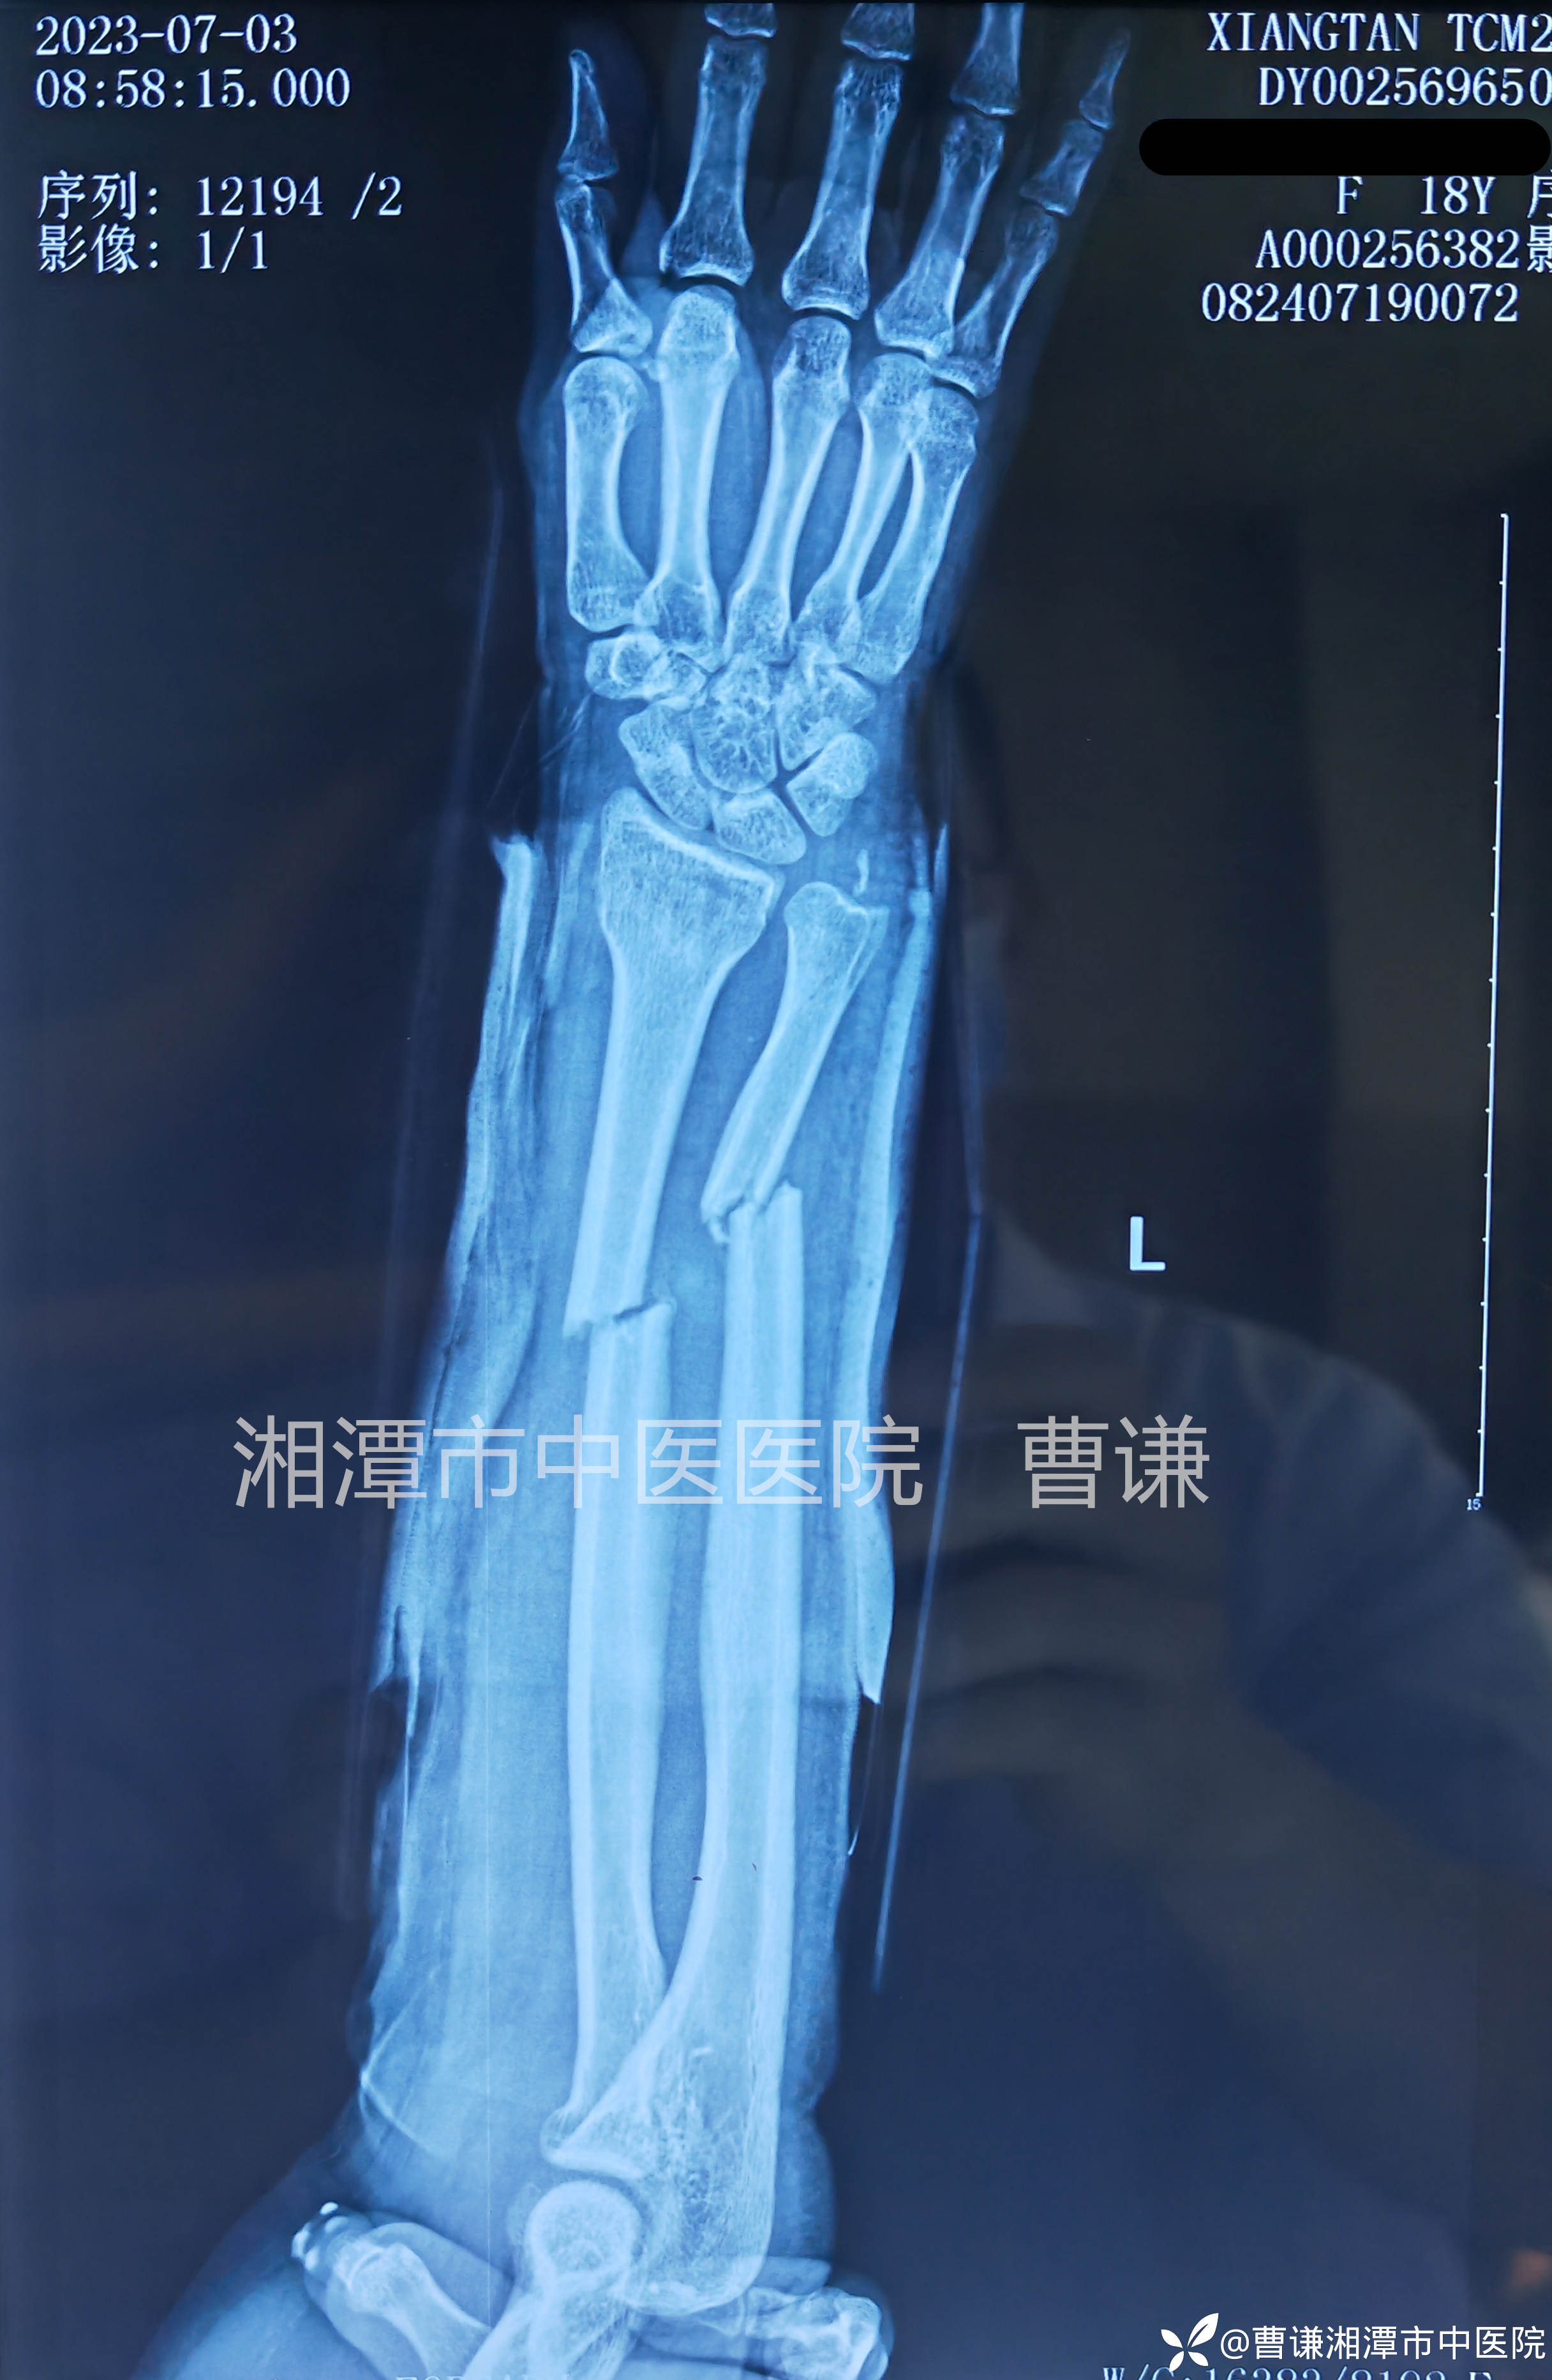

辅助检查:X线片:左尺桡骨中段骨折、左尺骨茎突撕脱骨折

临床诊断:左尺桡骨中段骨折、左尺骨茎突撕脱骨折

患者实习下班骑车跌倒致左前臂畸形、肿痛,活动受限,就诊我院,拍片示左尺桡骨中段双骨折,断端错位明显,建议手术治疗,但女孩不希望自己手臂留疤痕,坚决不同意手术治疗,要求保守治疗。